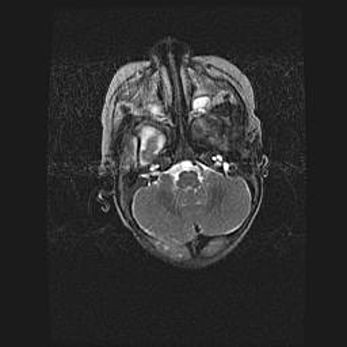

Подострая гематома правой гемисферы мозжечка.

Наружная гидроцефалия.

Возраст: 15 дней

Вес: 3100 г

Пол: женский

Окружность головы: 37 см

Срок гестации: 35-36 недель

При открытой наружной форме гидроцефалии у новорожденных расширяются и переполняются субарахноидные пространства.

Кровоизлияния в мозжечок имеют две клинико-анатомические формы: полушарные гематомы и кровоизлияния в червь.

К появлению этой патологии может привести: повреждения головного мозга, возникающие в результате асфиксии и гипоксии плода при беременности, или травмы во время родов. Редко гематома мозжечка может быть результатом первичной коагулопатии и сосудистой мальформации, диссеминированном внутрисосудистом свертывании, изоиммунной тромбоцитопении.